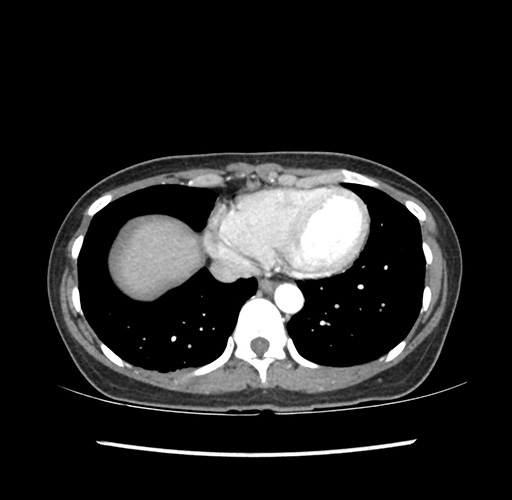

Imaging Analysis

Look through the patient's CT scan to identify any areas of concern for the necessary procedure.

Based on your CT findings, which issue(s) would give reason for "planned slowing down moment(s)" in this case?